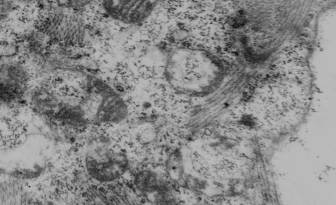

Расположенные в участках ишемии кардиомиоциты, которые еще сохраняли общую

клеточную структуру, при ультраструктурном исследовании выявляли выраженные

изменения митохондриального аппарата. В частности, митохондрии всех трех типов

имели признаки вакуолизации матрикса, фрагментации митохондриальных мембран,

значительного кристолизиса (рис. 1), [2].

Рис.1. Признаки вакуолизации матрикса, фрагментации

митохондриальных мембран, значительного

кристолизиса митохондрий кардиомиоцита левого

предсердия

крысы на 7-е сутки формирования экспериментального психоза.

Ув.: ×22000.